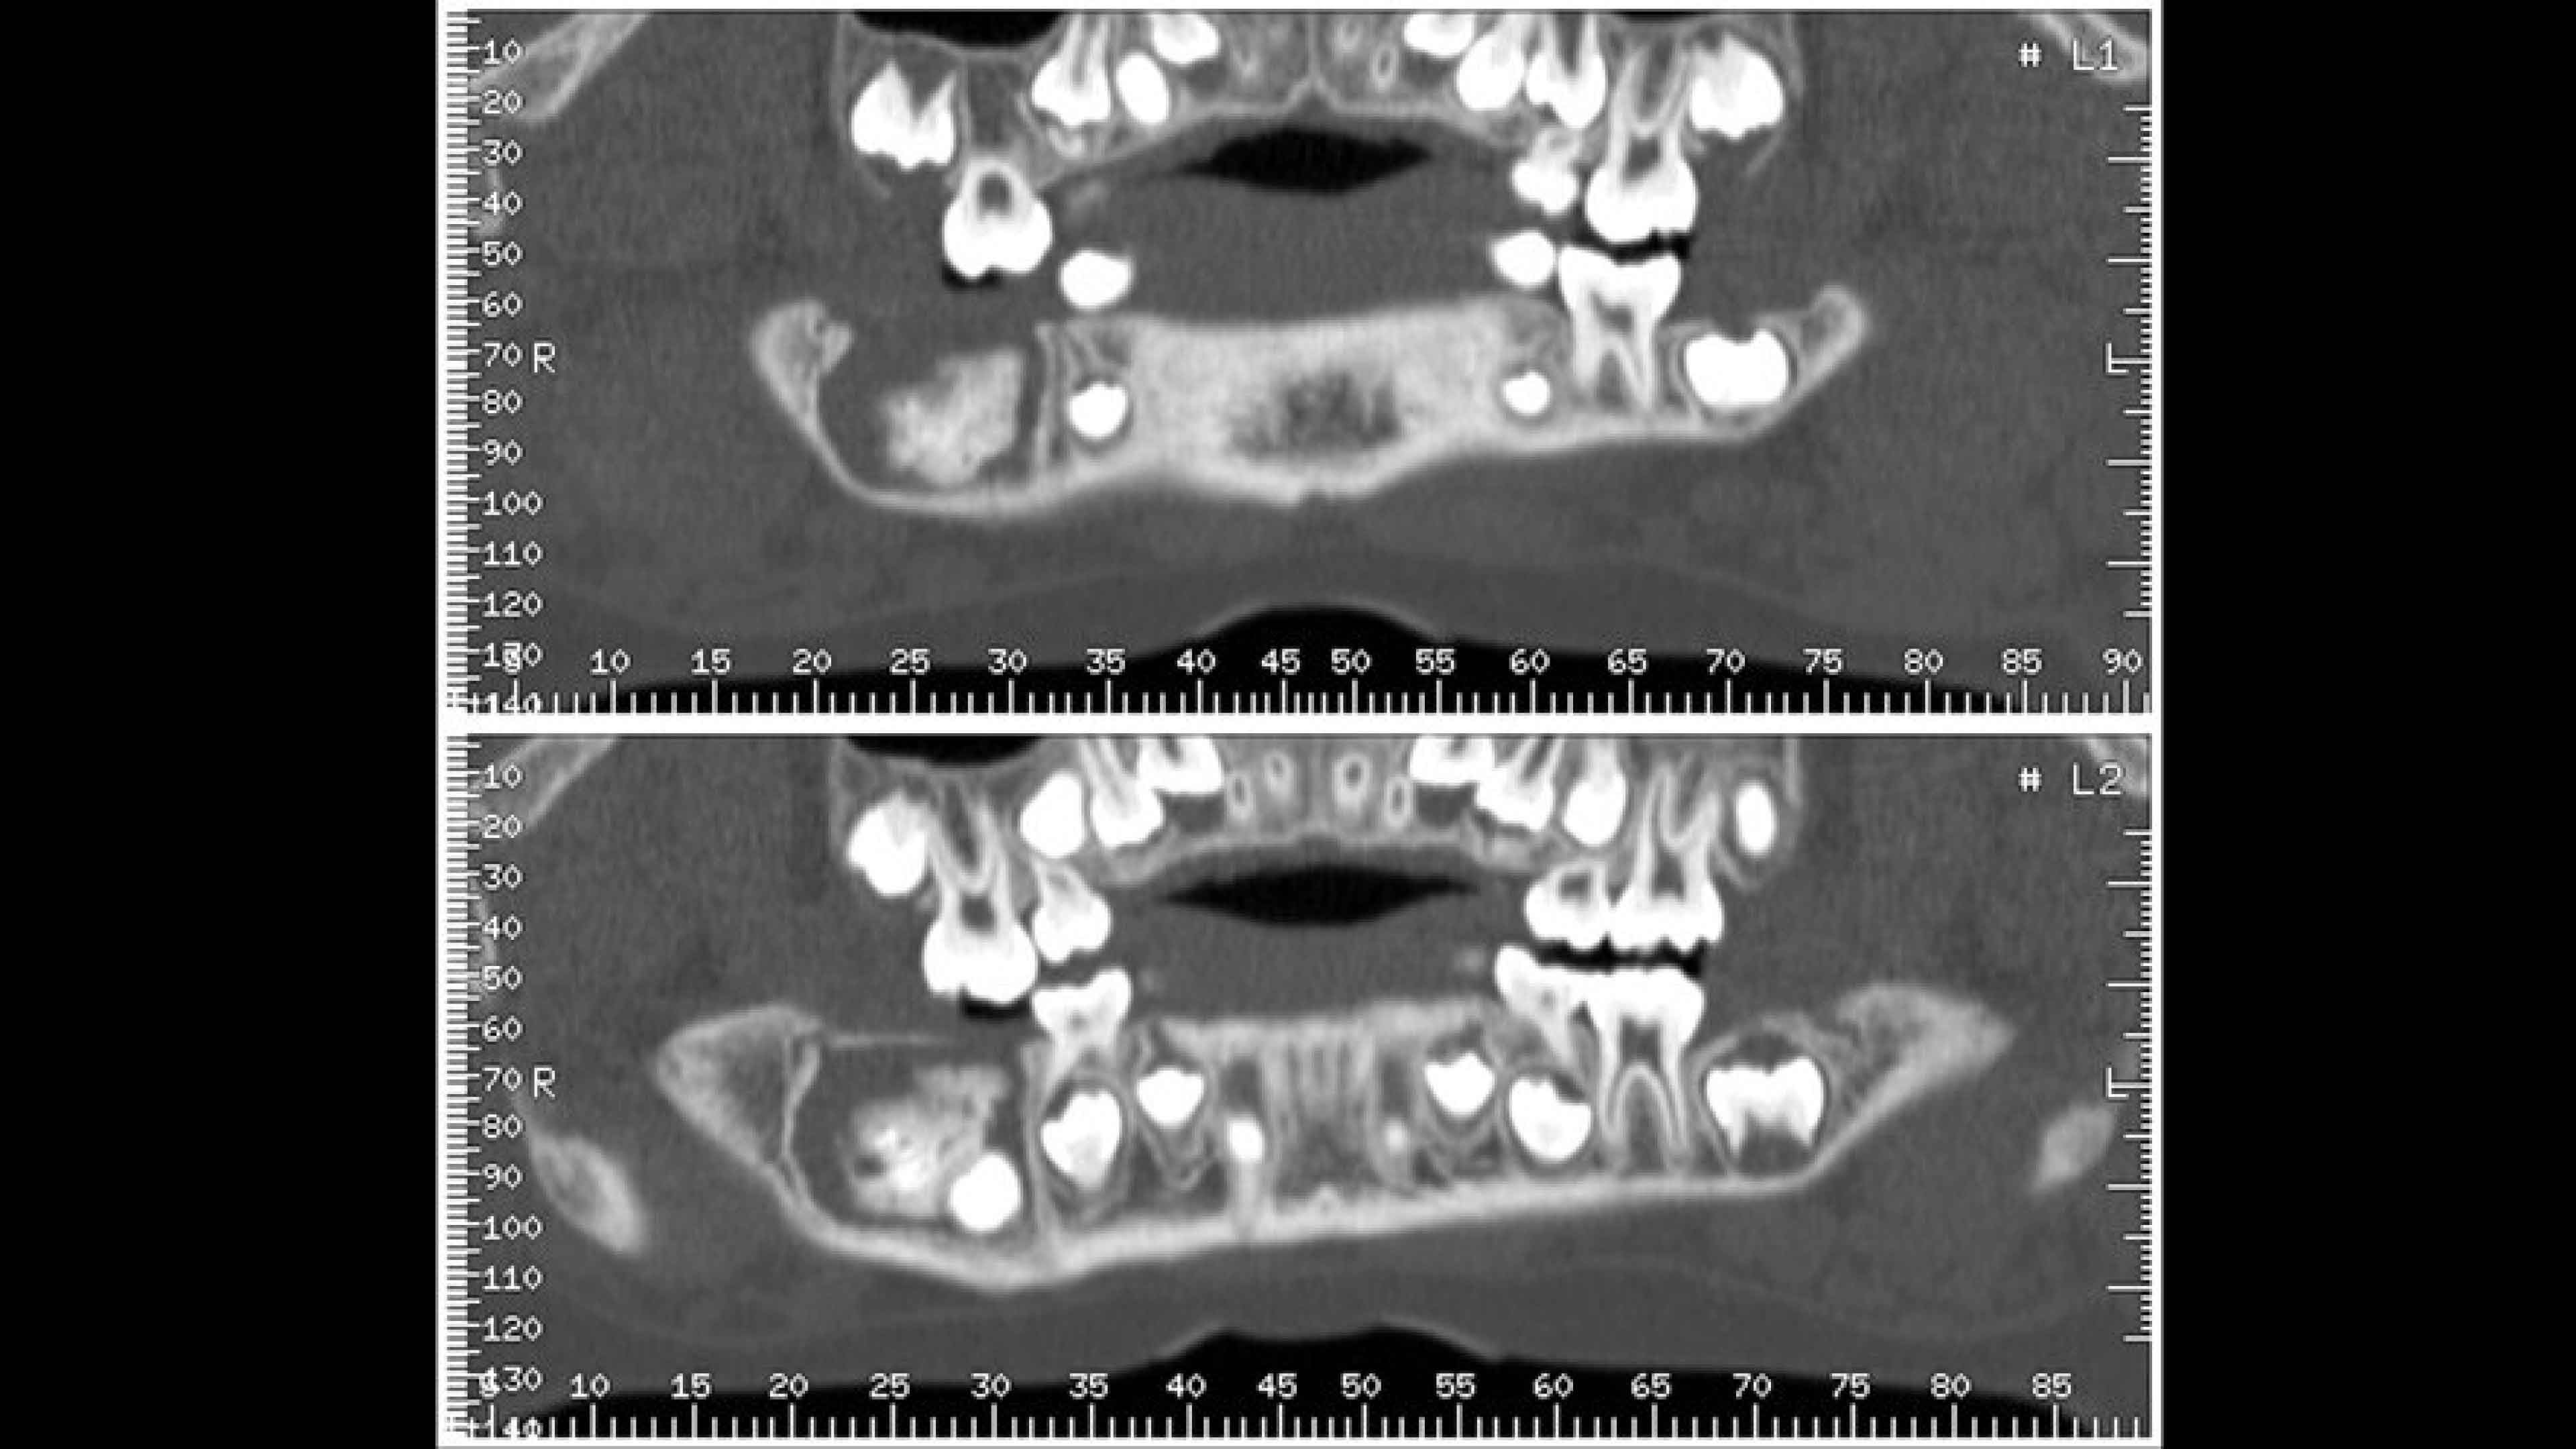

Panorex and oblique views

You can adjust or redraw curves used to generate views during the procedure

Cross-referenced views

Axial, panorex and oblique views remain cross referenced on the screen.

• The curve used to generate panorex and oblique views is drawn on selected axial views. It can be adjusted or redrawn easily at any time during Dentascan procedures.

• Axial panorex and oblique views remain cross referenced on the screen. Oblique views are generated in real time when the cursor is moved on axial or panorex views. A similar feature exists when the cursor is moved on a panorex or oblique view.

• A mm-scale is printed on the side of oblique and panorex views for direct measurement from film. The entire study is annotated to assist in film interpretation.